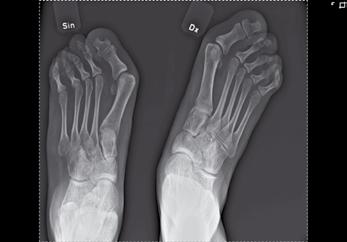

Figur 1a-d. Belastade fotbilder hos patient med bilateral spastisk cerebral pares med tydlig abduktion av framfoten på höger sida(fig 1a), där man på sidobilden (fig 1b) ser ett tydligt ”midfoot break” Patienten går med tåisättning på båda fötter och uppvisar tydlig hallux valgus bilateralt. Fig 1c visar peroperativa röntgenbilder, där laterala delen av foten förlängts genom insättning av strukturellt bengraft någon centimeter från leden mot cuboideum. Fig 1 d visar MTP I artrodes med stiftfixation på samma fot.

Obalans och överaktivitet

Ofta är spetsfotsställningen kombinerad med en adduktion eller abduktion av framfoten vilket vanligen brukar förklaras med muskulär ”obalans” eller ”överaktivitet”. Den muskulära obalansen ändras ofta med tiden, och en varus-adductusfot hos ett 4-5 årigt barn kan ett par år senare ha blivit en valgusfot, där framfoten istället kommit att svänga ut i abduktion (fig1a, 2a). Generellt tenderar valgusställning (eller snarare ökande framfotsabduktion) att tillta med ökande ålder under uppväxten och det är därför som en alltför tidig och ambitiös förflyttning av hela tibialis anteriorsenan lateralt lätt kan åstadkomma en överkorrektion.

Figur 2a och b. Patient med valgusbelastad fot och hallux valgus interfalangeus Postoperativ bild där calcaneus förlängts så att framfotsabduktionen försvåras. Stortån har åtgärdats genom en kilosteotomi på grundfalangen.

och övriga framfoten glider på det rundade talushuvudet varvid mediala ligamentapparaten successivt blir alltmer uttänjd (fig 1) samtidigt som peroneusmuskulaturen bidrar till abduktionsställningen. Vanligen står inte hälarna inte så kraftigt i valgus inledningsvis, men detta kommer ofta med tiden. I och med att framfoten vid belastning pekar mer lateralt minskar plantarflexorernas möjlighet att hålla emot underbenets strävan framåt över foten, och risken för knäande gång ökar därvid ytterligare. Speciellt hos barn med sämre gångförmåga tillkommer med tiden också ofta en utåttorsion av underbenen och ibland även en valgusställning i själva talocruralleden. En idag vanlig operationsmetod, för att på barn med måttlig framfotsabduktion motverka naviculares lateralglidning på talus, är en förlängningsosteotomi på calcaneus 1-2 cm bakom calcaneocuboidleden. Efter att osteotomispalten bänts isär införes en kil av trikortikalt cristaben eller annat strukturellt bengraft (fig 1c, 2b). Är detta otillräckligt (som t.ex. vid samtidig ledlaxitet) kan foten stabiliseras ytterligare genom talonaviculär artrodes. För de mest felställda och rigida fötterna kan trippelartrodes bli aktuell.

Stortåproblem är vanliga hos de lite äldre barn som fortsätter att gå med tåisättning av foten. Vanligen är felställningen störst på MTP-nivå (fig 1a), men ibland består den huvudsakliga prolemet av en hallux valgus interfalangeus med clavusbildning motsvarande IP-leden (fig 2a). För att nå bestående resultat av hallux valgusingrepp kan det vara klokt att överväga MTP I artrodes (fig 1d) eftersom felställningen annars tenderar att återkomma om barnet fortsätter att gå med tåisättning.